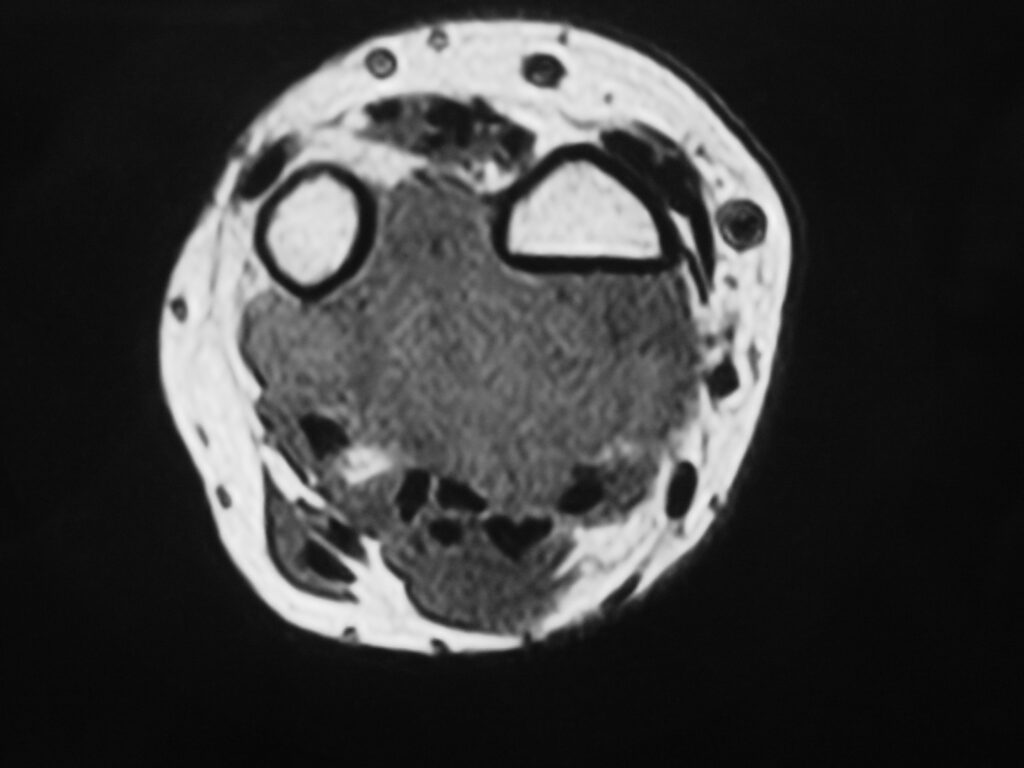

MRI

Shows multiloculated, heterogeneous mass.

“Triple Signal Intensity sign”; hypointense, isointense and hyperintense with fat on T2 – weighted MRI imaging. This sign is present in 30 to 50% of the cases. (Fig.3)

Under contrast enhancement Synovial Sarcoma appears heterogeneous and demonstrate areas of nodular enhancement.

In approximately 30% of cases a multiple vascular cannel may be identified

Synovial sarcomas may have a cystic appearance and are often mistaken for ganglion cysts especially those adjacent to tendons and in the foot and ankle.